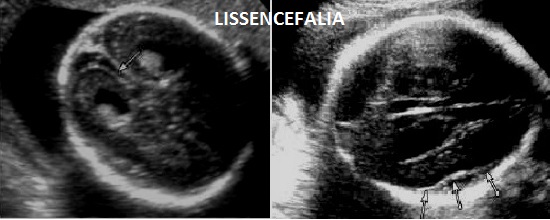

La Sindrome di Neu-Laxova (lissencefalia tipo III) è una rara sindrome plurimalformativa a trasmissione autosomina recessiva.

E' caratterizzata da grave ritardo di crescita intrauterino, grave microcefalia, lissencefalia tipo 3  e dismorfismi facciali consistenti in ipertelorismo, micrognazia, grave esoftalmo, anomalie auricolari, naso piatto; una caratteristica è l'edema spiccato che interessa cranio, gomiti, ginocchia, mani e piedi (si ha quasi l'impressione che le dita siano assenti); vi è inoltre assenza dei movimenti attivi fetali (SAF) e possono esservi contratture articolari (artrogriposi) caratterizzate da arti superiori ed inferiori in flessione.

2. microcefalia grave,

6. lissencefalia tipo 3,